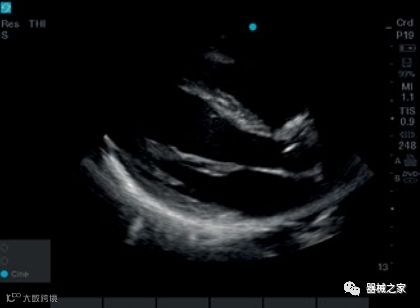

2018年,GE医疗集团发布了其cSound图像重建技术的Imaging Elevated版本。该技术有助于Vivid E95心脏成像系统的成像质量,工作流程和量化。它利用GPU处理来提高音量帧速率,GE称为音量最大值或Vmax。与上一代系统相比,这使得TEE的帧速率几乎可以达到三倍。